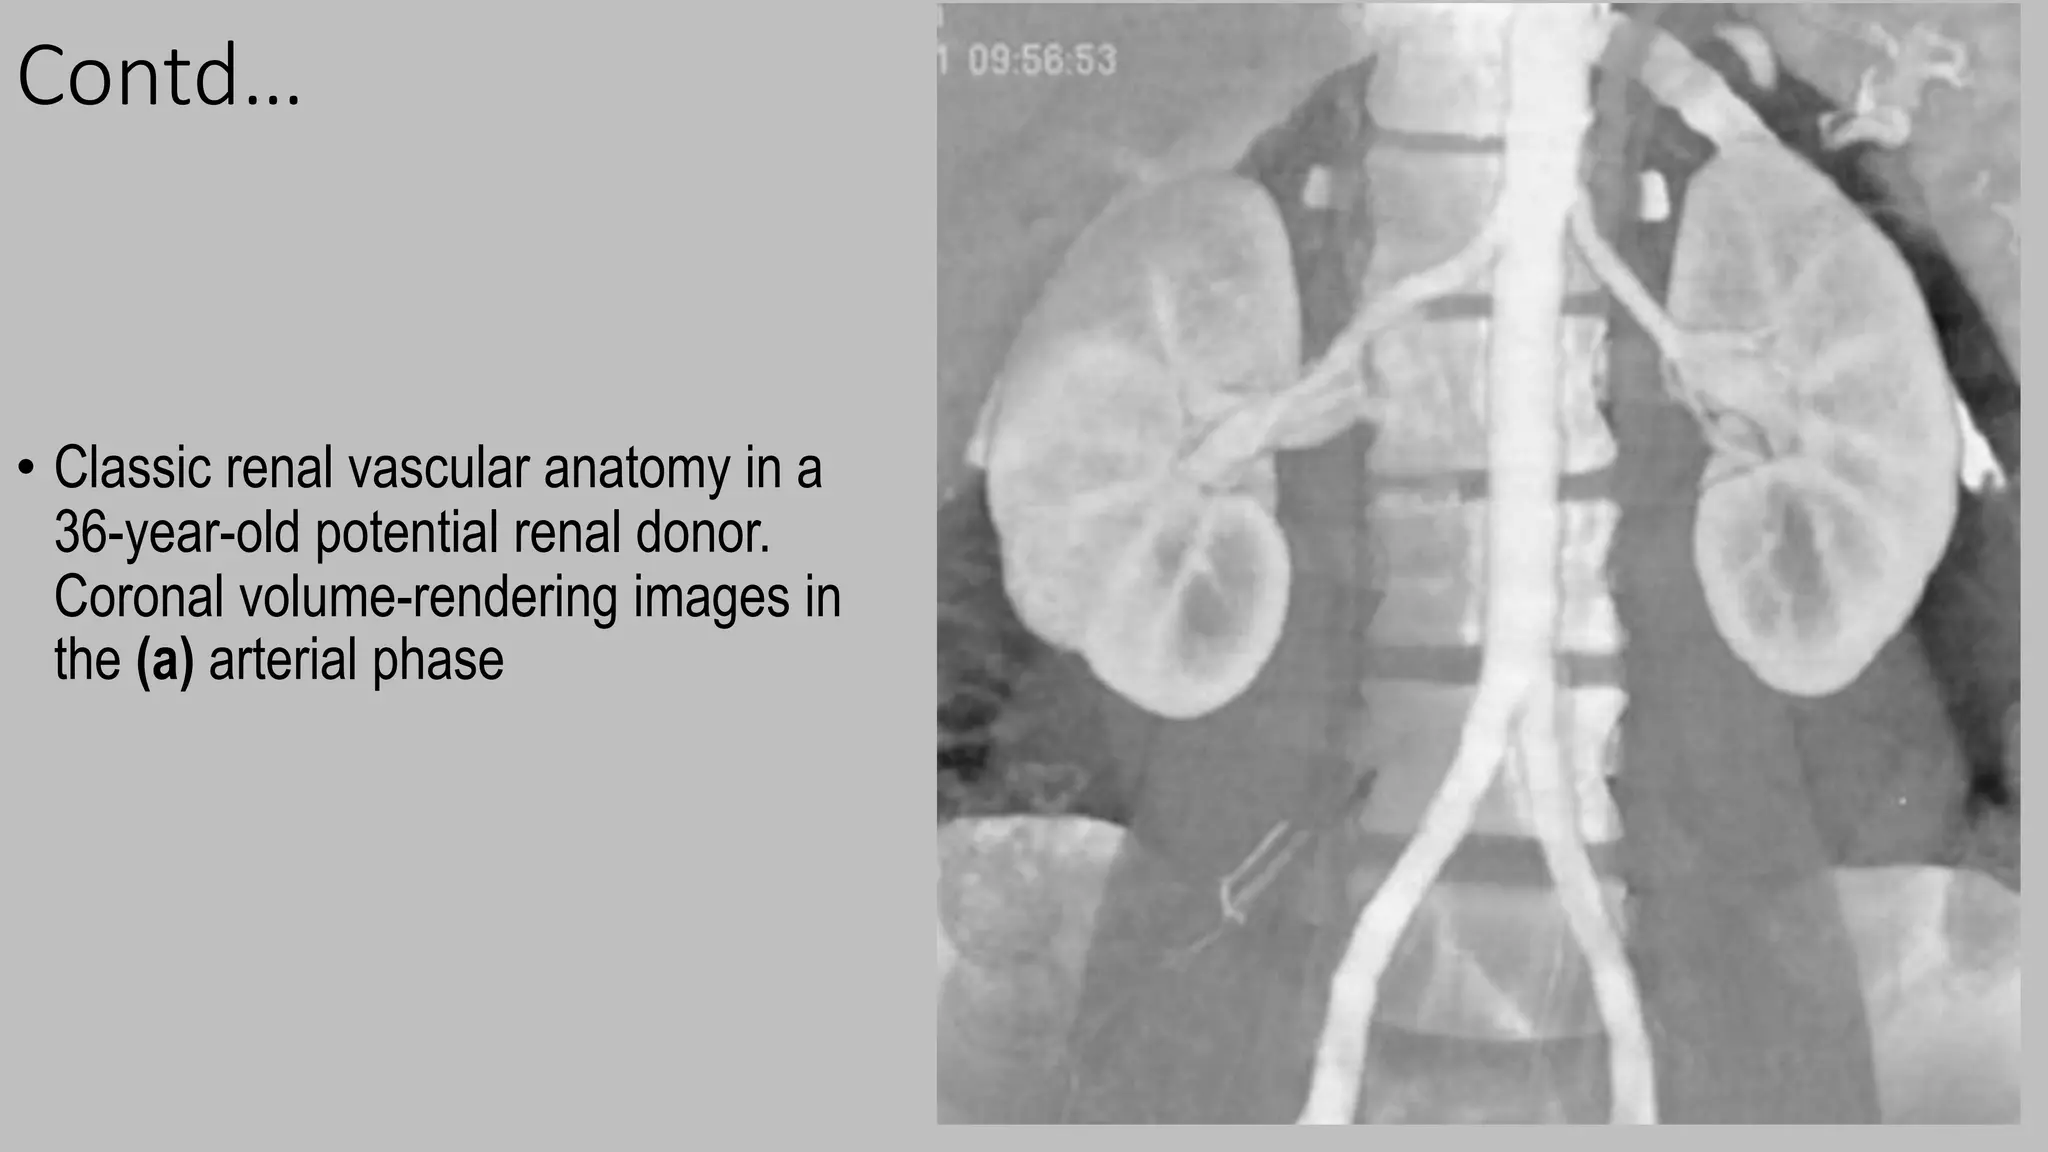

• Classic renal vascular anatomy in a

36-year-old potential renal donor.

Coronal volume-rendering images in

the (a) arterial phase

Contd… • Classic renalvascular anatomy in a 36-year-old potential renal donor. Coronal volume-rendering images in the (a) arterial phase